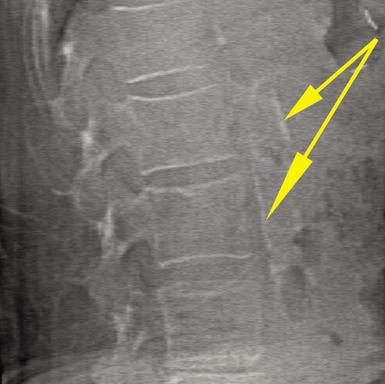

- High-Definition Instant Vertebral Assessment (IVA-HD) capability for significantly improved detection of vertebral fractures;

- An Abdominal Aortic Calcification feature through Hologic's IVA-HD technology, which enables clinicians to visualize abdominal aortic calcifications, a significant predictor of cardiovascular disease; and